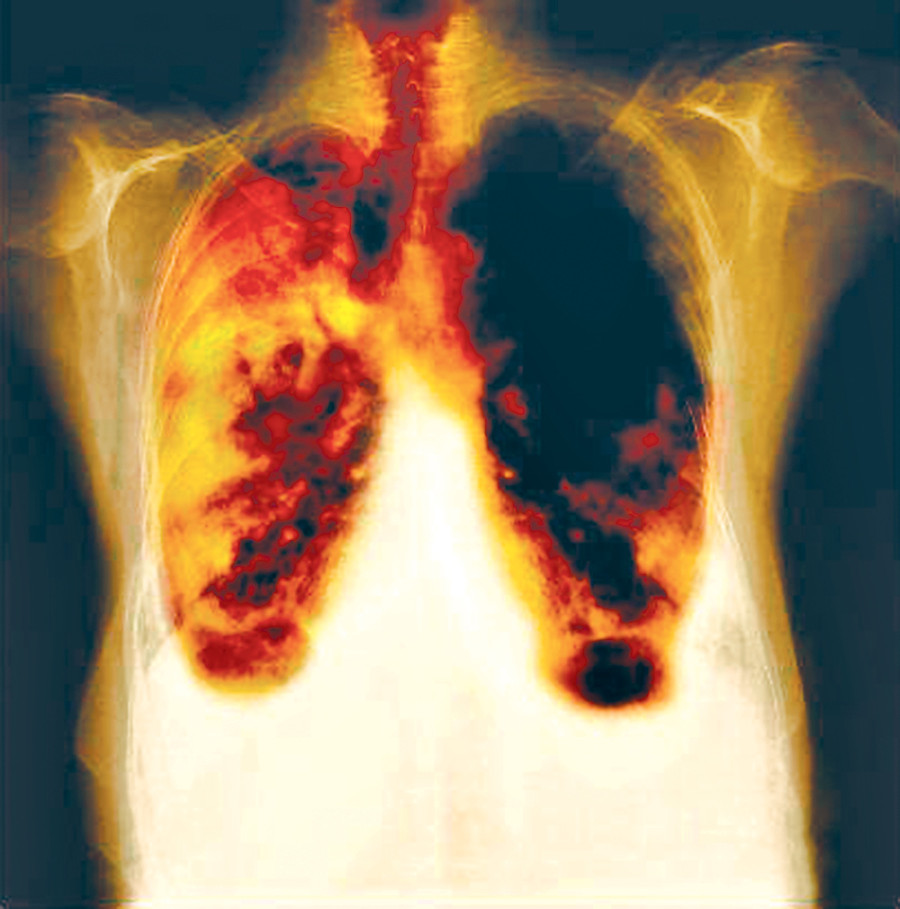

The reason behind the growing use of asbestos in the Tarai is misleading advertising. People were told that asbestos is the best construction material, is easy to fix, provides warmth in the winter and remains cool in the summer. Asbestos is being freely imported, marketed, promoted and used in Nepal despite being legally banned since June 20, 2015. All types of asbestos cause lung cancer, mesothelioma, cancer of the larynx and ovary and asbestosis (fibrosis of the lungs). Exposure to asbestos occurs through inhalation of fibres in the air in the working environment, ambient air in the vicinity of point sources such as factories handling asbestos or indoor air in housing and buildings containing friable (crumbly) asbestos materials.

Currently, about 125 million people in the world are exposed to asbestos at the workplace. In 2004, asbestos-related lung cancer, mesothelioma and asbestosis from occupational exposures resulted in 107,000 deaths and 1,523,000 disability adjusted life years, according to the World Health Organisation. Asbestos is classified as a known human carcinogen. Asbestos fibres are microscopic and, therefore, are easily inhaled. Once inhaled, the fibres stick to the respiratory system, including the lining of the lungs and inner cavity tissue. As asbestos fibres are typically quite rigid, they become lodged in the soft internal tissue of the respiratory system, and are not easily expelled or broken down by the body. Over time, these fibres can accumulate and cause scarring and inflammation, which can affect breathing and lead to serious health problems.